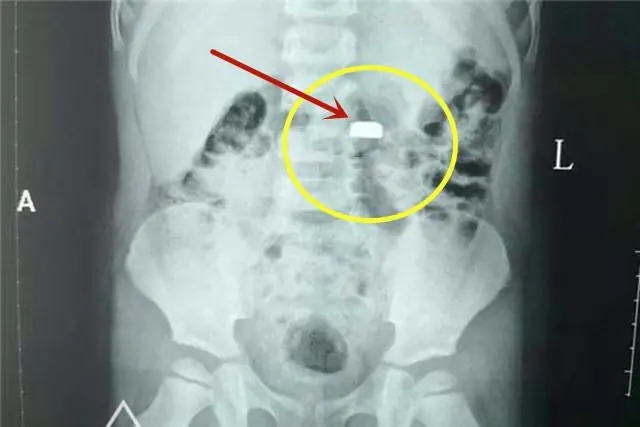

กลายเป็นอุทาหรณ์ที่พ่อแม่ทั่วโลกต้องฟัง! เมื่อคุณแม่ชาวจีนชื่อ "หลินหลิน" ต้องเผชิญกับสถานการณ์บีบคั้นหัวใจ เมื่อลูกชายวัย 3 ขวบ เผลอกลืน "ถ่านกระดุม" (Button Battery) จากเครื่องแคะหูไฟฟ้าเข้าไป แม้คนในบ้านจะมองว่า "เรื่องเล็ก" แต่สติของคุณแม่คนนี้ช่วยให้ลูกรอดพ้นจากการสูญเสียครั้งใหญ่

ส่งโรงพยาบาลด่วนที่สุด: แจ้งหมอทันทีว่าสงสัยว่าลูกกลืนถ่าน เพื่อรับการเอกซเรย์และส่องกล้องออกทันที